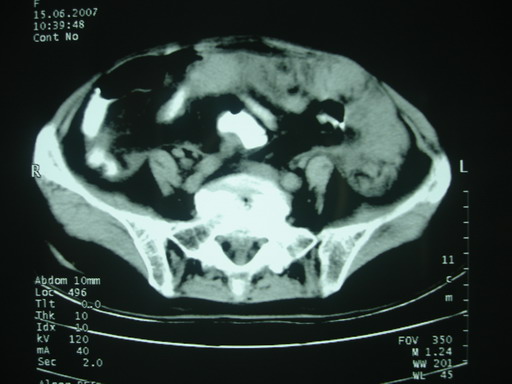

女,70岁,自述锻炼时牵拉导致左下腹疼痛,后疼痛加剧,发现包块10天,家属说其他检查,无法热,大便正常,一般情况差,痛苦面容,左下腹压痛明显,口服造影剂后腹泻,钡灌肠降结肠迂曲粘膜未见异常。抗炎治疗一周后诉症状减轻。

以下图考虑是何病?谢谢!

大网膜血肿?建议增强进一步检查。

支持大网膜血肿

盆腔附件区不规则软组织密度影,与下腹部异常密度影相联,建议进一步检查除外妇科疾患!